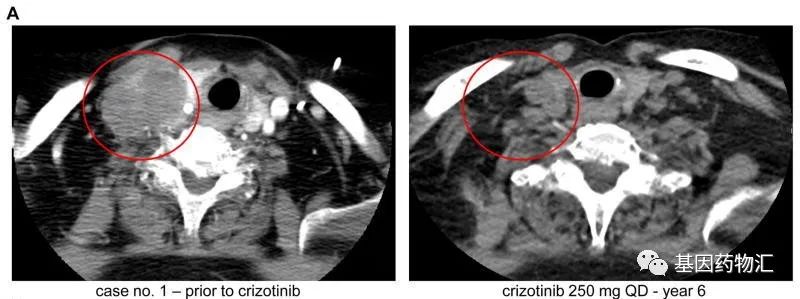

10年、11年、12年,三位长期生存的非小细胞肺癌患者,共同点有什么?

这一次,基因药物汇将与大家一起分享三份案例报道——这些案例有一个相同的特点,那就是,在多线、多类型的复杂治疗的努力之下,患者的生存期都超过了十年,是长期荷瘤生存者!...